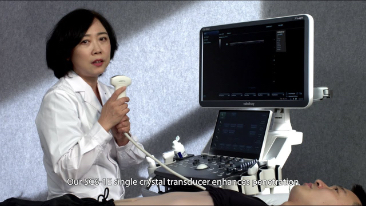

As solu??es de imagem geral Mindray Resona ajudam mĂŠdicos a obter resultados mais precisos e eficientes de diagnĂłstico e tratamento por meio de sondas de aplica??o de subdivis?es abrangentes e ferramentas eficientes de aplica??o clĂnica.

Produtos para imagem geral